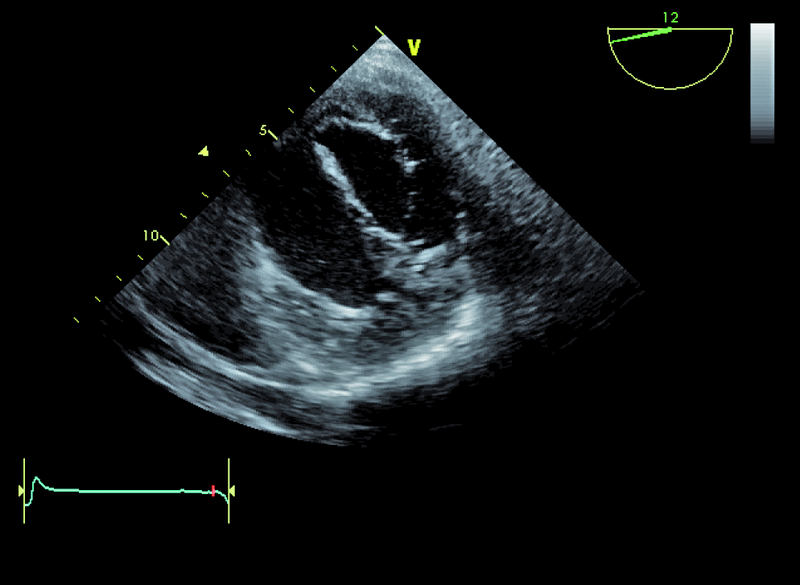

Niedomykalność zastawki mitralnej o etiologii niedokrwiennej pogarsza rokowanie u chorego z chorobą wieńcową i istotnie obniża komfort życia. Fala zwrotna w prezentowanym materiale sięga ujścia żył płucnych (ryc. 1), a ciśnienie w jamie prawej komory jest podwyższone (ryc. 2). U chorych, u których nie ma wskazań do rewaskularyzacji lub u chorych z chorobami współistniejącymi poszukuje się innych metod interwencji poza chirurgiczną naprawą. Punktem wyjścia dla rozważań o możliwości leczenia niechirurgicznego jest dokładna ocena anatomii zastawki. Wykorzystuje się dane zarówno z badania przezklatkowego, jak i przezprzełykowego, choć oczywiście optymalnym rozwiązaniem byłoby zastosowanie obrazowania trójwymiarowego. Sporo uwagi poświęca się ostatnio naprawie płatków zastawki za pomocą tzw. urządzenia mitraclip. Techniką tą można interesować się zwłaszcza w kontekście chorych bez istotnego poszerzenia pierścienia zastawki (w prezentowanym przypadku średnica pierścienia nie przekraczała 35 mm), a z dostatecznie dużą ilością tkanki tworzącej jej płatki. Założeniem techniki mitraclip, przypominającej zabieg chirurgiczny Alfieriego, jest połączenie segmentów środkowych płatka przedniego i tylnego. Skutecznie wykonany zabieg poprawia koaptację płatków i zapoczątkowuje odwrotny remodeling lewej komory, zmniejszający z kolei udział tzw. sił pociągających. Na co trzeba zwrócić uwagę, oceniając pacjenta z niedomykalnością mitralną, towarzyszącą chorobie niedokrwiennej? Niedomykalność (wg podziału Carpentiera typ 3b) powinna rzeczywiście powstawać między segmentami A2 a P2 (ryc. 3), ponieważ tylko w takim wypadku połączenie płatków i wytworzenie dwóch osobnych ujść może choremu przynieść korzyść. Ważnym elementem oceny jest uzyskanie projekcji przezżołądkowej poprzecznej. Ta projekcja bardzo dobrze ilustruje wielkość płatków i ich wzajemną relację (ryc. 4 – większy płatek tylny znajduje się bliżej głowicy). Przeciwwskazaniami do zabiegu implantacji mitraclip może być nadmierna grubość płatków, utrudniająca ich uchwycenie przez ramiona urządzenia, mniejsza niż 2 mm długość koaptacji oraz większa niż 11 mm głębokość koaptacji w stosunku do linii podstawnej pierścienia zastawki. Wymienionych cech nie potwierdzono w badaniu (ryc. 5, 6) i zakwalifikowano chorego do zabiegu w trybie planowym. Warto pamiętać, że echokardiografia służy nie tylko ocenie wskazań do zabiegu, ale stanowi także podstawę jego monitorowania.